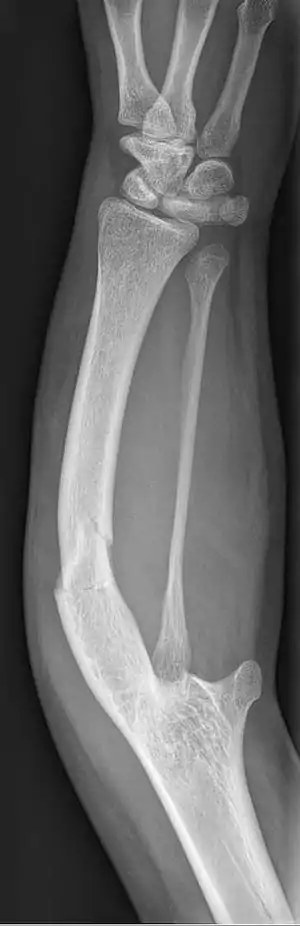

Ulnar dysplasia also known as ulnar longitudinal deficiency, ulnar club hand or ulnar aplasia/hypoplasia is a rare congenital malformation which consists of an underdeveloped or missing ulnae bone, causing an ulnar deviation of the entire wrist. The muscles and nerves in the hand may be missing or unbalanced. In severe cases, ulnar digits (e.g. ring and pinky finger) may be missing. Sometimes, radial dysplasia occurs alongside this malformation.[2] This condition occurs in 1 in 100,000 live births.[3][4][5][6] Sometimes, other orthopedic problems occur alongside this malformation, such as scoliosis.[7]

| Ulnar hypoplasia | |

Type 2: The ulnae is moderately-severely smaller than normal. The radius is deviated and so is the hand

Type 3: The ulnae is completely missing. The radius is even more deviated, causing a severe ulnar deviation of the hand.